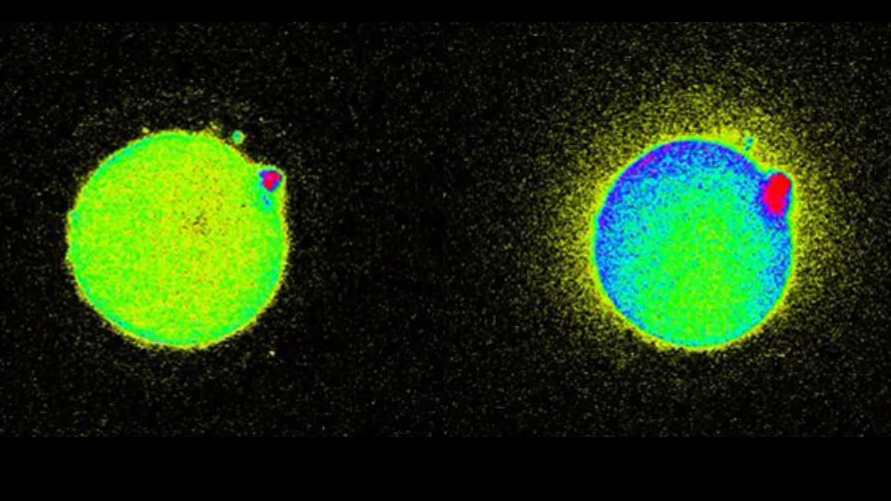

The team injected an egg with sperm enzyme. (The use of actual sperm in experiments is illegal.) Doing this triggers an increase in calcium within the egg that then causes zinc to be released. The zinc binds to small molecule probes, that emit light that can be seen under a fluorescence microscope as a spark. From there, millions of zinc molecules explode momentarily all around the outside of the egg.

Being able to observe all this, and non-invasively, is important because zinc is critical for the development of a healthy embryo, and Northwestern has previously established that zinc is actually what triggers an embryo to grow and change into a distinct new organism, that is, a new person.